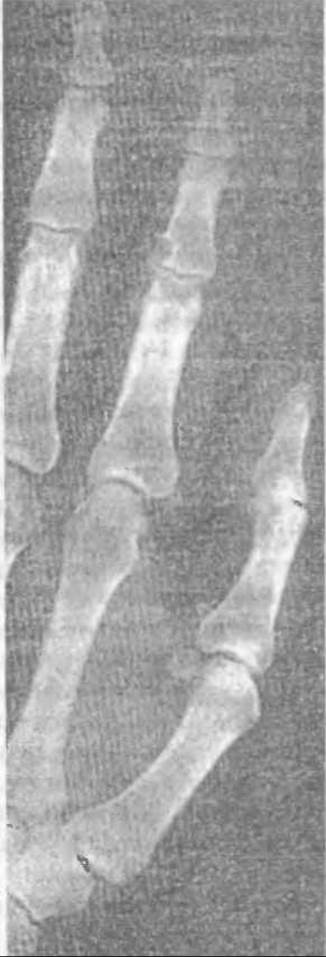

При біохімічному дослідженні виявляють характерну гіперурикемію. Патогномонічним симптомом подагри є наявність кристалів сечової кислоти у тканинах, які інколи можна побачити через потоншену шкіру біля суглобів (мал. 323) або при гістологічному дослідженні подагричних вузликів (мал. 324).

Мал. 323. Трофічні зміни шкіри при подагрі з просвічуванням кристалів сечової кислоти біля суглобів кистей рук.

Слід відзначити, що з часом (з роками) змінюється характер нападів. Рецидиви бувають частішими у хворих із підвищеними показниками сечової кислоти у плазмі (більше 9-10 мг%), тривають щоразу довше, а явища запалення декількох суглобів чимраз більші. Якщо після першого нападу може не залишитись жодних слідів на ураженому місці, то з кожним наступним кількість кристалів, які відкладаються у тканини, збільшується, утворюючи характерні вузли (tophi) навколо суглобів. Вони навіть можуть з часом просвічуватись через потоншену шкіру, особливо на пальцях рук (мал. 323). Хвороба клінічно проявляється як подагричний поліартрит, затягується і стає хронічною.